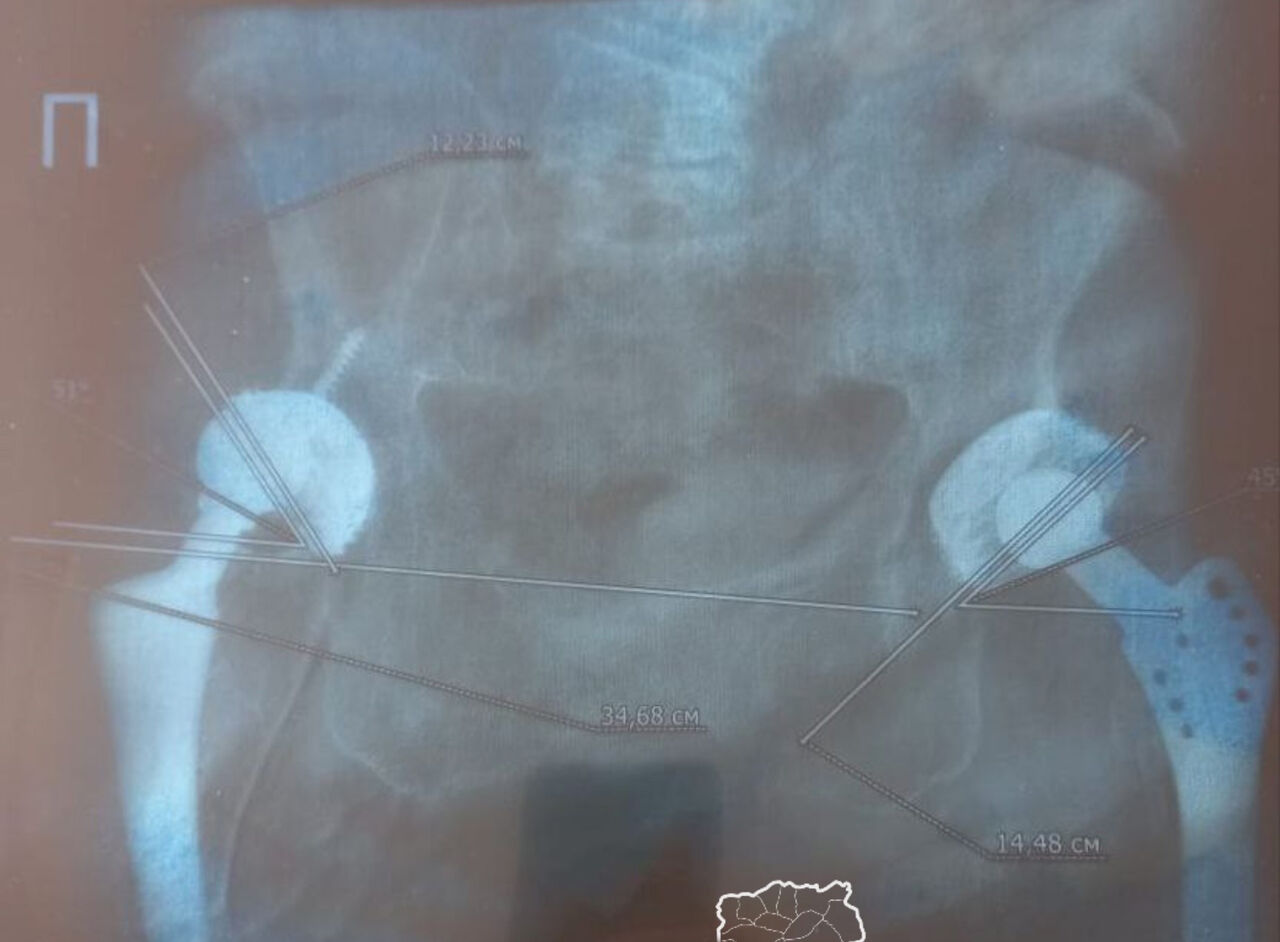

В 1992 году женщина решила оставить работу из-за болей в суставе левой ноги. Как рассказала горожанка, в 1998 году в Ленинске-Кузнецком в Центре охраны здоровья шахтеров ей выполнили первую операцию по замене сустава. Через семь лет пришлось заменить сустав также на правой ноге.

В 2022 году киселевчанка попала в ту же больницу с вывихом вкладыша правой ноги. Тогда менять конструкцию не стали, кроме того, в выписке указали не ту ногу.